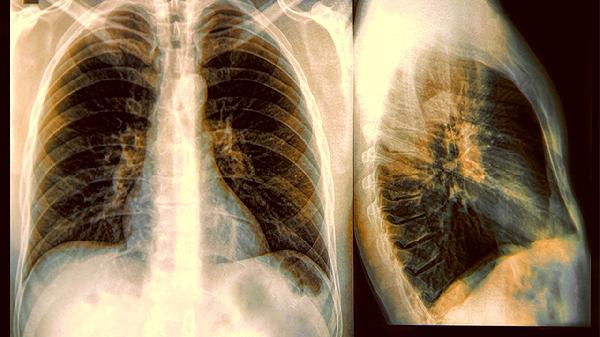

打开体检报告看到"肺结节"三个字时,很多人都会心头一紧;当医生建议手术切除时,焦虑感更是直线上升。其实肺结节就像肺部的小疤点,绝大多数都是良性的,手术切除后的五年存活率能达到90%以上。但手术后不注意保养,结节这个小捣蛋鬼还是可能卷土重来。